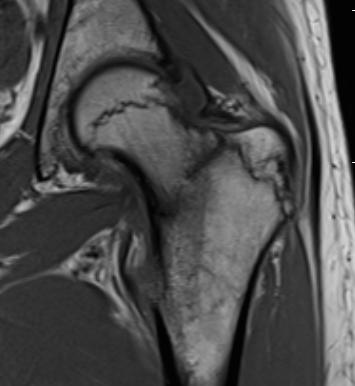

MRI

Edema / fracture line / hip effusion

MRI demonstrating edema likely across entire neck

MRI demonstrates complete fracture